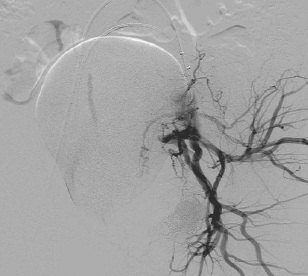

女性盆腔血管分布图

女性盆腔血管分布主要:是膀胱、生殖器官和直肠、是植物神经功能紊乱、事站立工作、子宫后位、长期便秘、早婚早育、孕产频繁的人,以及患有盆腔炎、附件炎、子宫内膜炎等炎症时,静脉血流量增多,盆腔静脉压力增高,影响静脉回流,也容易导致充血。 一般女性在性兴奋时,大量血液涌入盆腔组织,形成充血状态。如果未能达到性高潮,则盆腔充血状态消退很缓慢,会出现下腹坠胀、酸痛等不适。